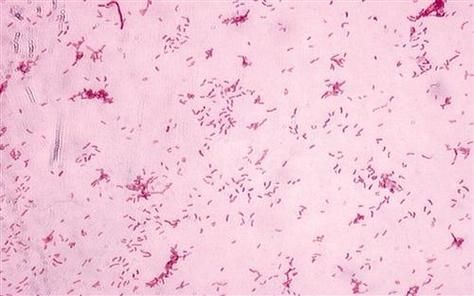

壓養環境下,龍魚因高密度、低溶氧、水質惡化而免疫力驟降,極易成為致病菌的溫床。中國疾控中心明確指出,淡水觀賞魚(含龍魚)常攜帶以下人畜共患病原體:

- 嗜水氣單胞菌(Aeromonas hydrophila):常見于壓養龍魚體表黏液與水體中,可通過皮膚微小傷口(如刮傷、魚鰭刺傷)侵入人體,引發蜂窩織炎、壞死性筋膜炎,嚴重者可致敗血癥。

- 分枝桿菌(如海洋分枝桿菌):長期接觸污染水體可致皮膚肉芽腫,表現為緩慢擴大的紅腫結節,誤診率高,治療周期長達數月。

臨床案例顯示,部分患者因清理魚缸時不戴手套,手部傷口接觸龍魚分泌物后數日內出現紅腫化膿,確診為嗜水氣單胞菌感染。